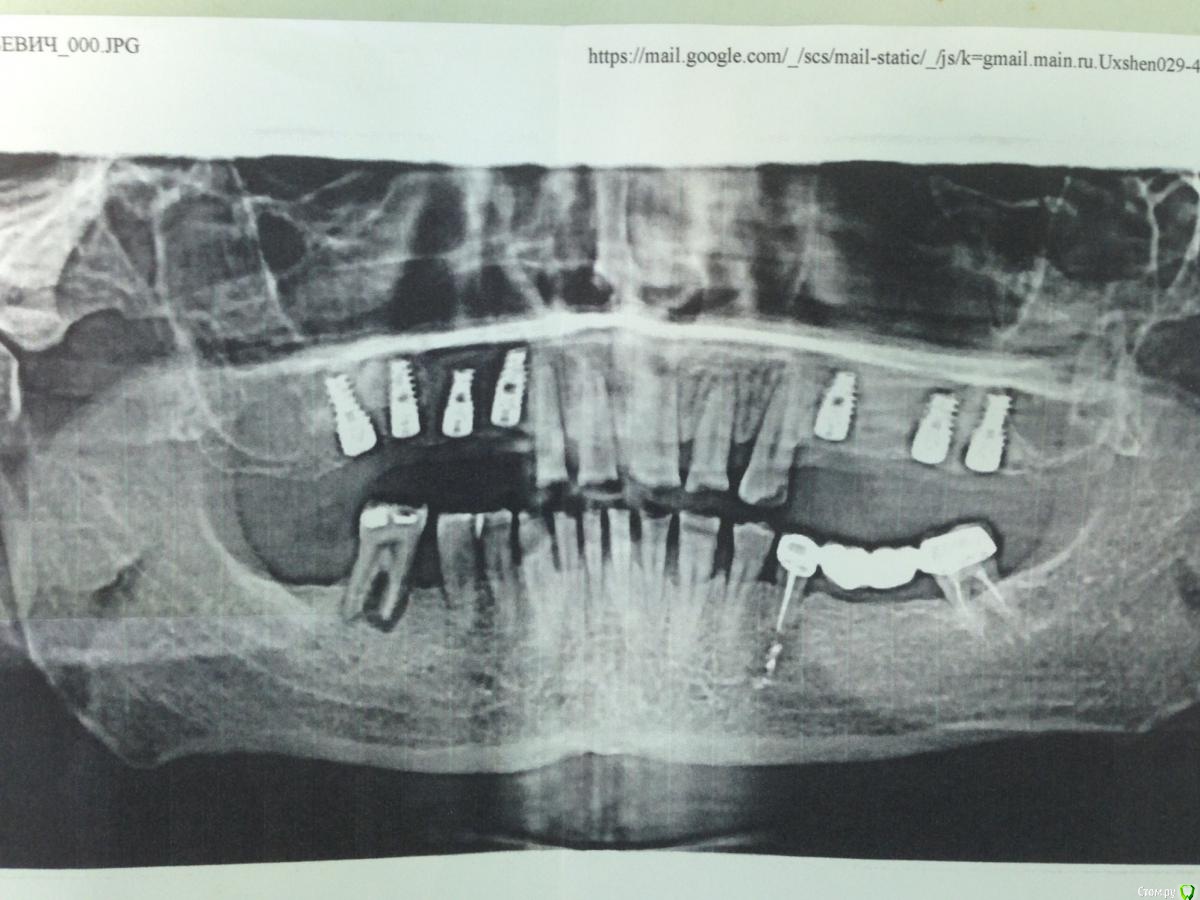

Pavel Опубликовано 24 марта, 2017 Поделиться Опубликовано 24 марта, 2017 Пришёл пациент. Второй год ездит в Москву из наших краёв. Были два синуса, импланты. Даже была попытка ортопедического этапа на В/ч. Мосты ему не понравились, так как по его мнению не видны зубы из-под верхней губы, как он ожидал. Переделывать ему там отказались, в общем он от них ушёл. Почему ещё не установлены импланты 46 и 47 на н/ч мне не понятно. Пациент курит. Курит много.Просит взять его, но я отказываюсь. Первое - не работаю по имплантам с курильщиками. Но основная причина в том, что мне не понятно, кто будет отвечать за возможный уход имплантов, если ортопедическая работа на них будет стоять моя. Боюсь, что возникнет известная ситуация - "кто последний, тот и папа". Ситуация щекотливая. Договорами и только договорами защищаться от пациентов мы здесь не привыкли, не наш метод. Поэтому я от его протезирования отказался. Тем более, как показалось на его бумажном снимке, с имплантами не полный порядок.( возможно это результат бумажности снимка, где всё разрешение теряется). Обещал лишь пациенту посоветоваться на форуме, как ему дальше поступить, чтобы и не подставлять никого, и самому получить реальный результат, защищённый хоть какими-то гарантиями. Порекомендовал всё же вернуться в клинику, где всё это делал и там продолжать в конструктивном ключе.Ваше мнение, коллеги. Как поступить пациенту в клиническом плане и чтобы не грузить никого лишними никому не нужными юридическими последствиями. Ссылка на комментарий